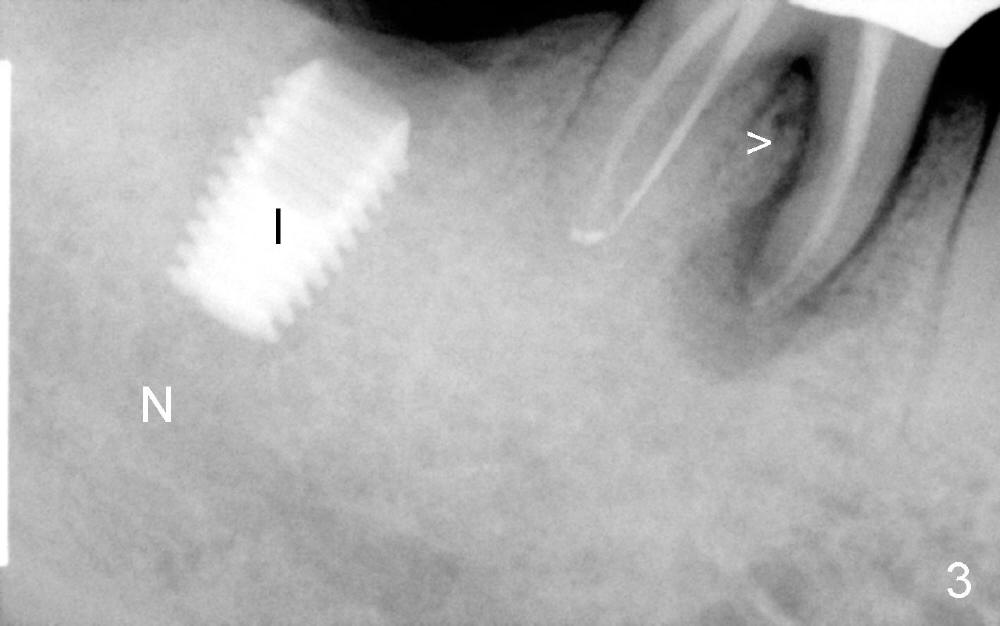

三十一号牙植牙前再次向病人解释应该先拔除三十号牙(根裂),他仍想不通,强调他没有任何症状,万一出现问题,似乎我们双方愿意承当责任。CT检查表明植牙处骨头高度不够,准备植入Bicon 6x5.7 mm植牙,厂家要求植牙应该埋在牙槽嵴下面2-3mm,总之,开始钻洞,深八毫米,当使用五毫米钻头时,颊侧骨板开始变薄,这时骨头宽度不够,可能开始做osteotomy时太远离舌侧,直径六毫米植牙不合适了, 哭也没用了,可以植入五乘六毫米植牙,但是这位病人可能有夜间磨牙(bruxism),又小又短植牙可能不行。

不妨先拍摄X光片看看,三十号牙近中根尖阴影好像没有那么可怕(图二A),但愿它能奇迹般自行愈合,免得造成邻牙植牙失败。三十一号牙钻头(R, reamer, 5 mm diameter, 8 mm deep)离下牙槽神经(N)大约四毫米(图二3是正在愈合第三磨牙拔牙窝),钻头以及植牙还可以往下走两三毫米,最后好像达到目的(图三 I:植牙),但是三十号牙近中病变惨不忍睹(箭头)。植牙后让病人口服Amoxicillin,期望三十号牙近中感染不至于蔓延到弱不禁风的植牙区,有没有感染灶邻近植牙成功病例?

以往挖空心思杜绝植牙附近病变,有个牙医认为那是overtreatment,可恨的是偶尔overtreatment也不能预防植牙出现问题,可能临床因素太多了。可能因为丧失原则,同一天给另外一位急诊病人在感染灶旁植牙,不知大家有耐心听my excuses (coming soon)?多谢!